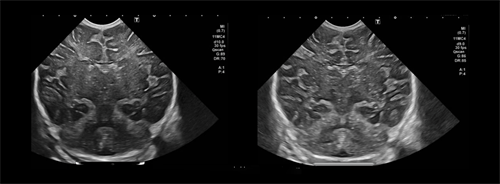

Este procedimento utiliza ultrassons de elevada energia, guiados por ressonância magnética, para actuar com precisão milimétrica em áreas específicas do organismo. A energia é concentrada num ponto exacto, provocando uma alteração controlada do tecido-alvo, sem afectar as estruturas circundantes.

O tratamento é realizado com o apoio de imagem em tempo real, normalmente através de ressonância magnética, o que permite ao médico identificar com precisão a zona a tratar e monitorizar o procedimento.

Ao concentrar a energia dos ultrassons num ponto específico, é possível gerar calor suficiente para actuar sobre o tecido, sem necessidade de incisões ou instrumentos cirúrgicos.